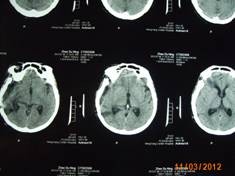

近日,一名來自常寧的58歲女性患者,因右側(cè)肢體麻木,頭暈3月入住衡陽(yáng)市中心醫(yī)院神經(jīng)外科。頭顱增強(qiáng)磁共振檢查明確右側(cè)中顱窩底巨大腦膜瘤,約10*6*5cm3大小。經(jīng)過嚴(yán)密的術(shù)前檢查和全科術(shù)前討論,以科室主任鐘三寶主任醫(yī)師為首的手術(shù)組經(jīng)過4個(gè)小時(shí)的顯微鏡下手術(shù),順利的全切腫瘤。因腫瘤巨大,瘤體切除后局部留下一很大空腔,容易并發(fā)腦組織移位、腦出血,導(dǎo)致嚴(yán)重并發(fā)癥。術(shù)者創(chuàng)新地使用了水囊,逐步減壓等方法,使患者平穩(wěn)地度過了腦組織復(fù)位關(guān)。術(shù)后未出現(xiàn)任何并發(fā)癥,恢復(fù)良好,順利出院。

(術(shù)后復(fù)查患者恢復(fù)順利)